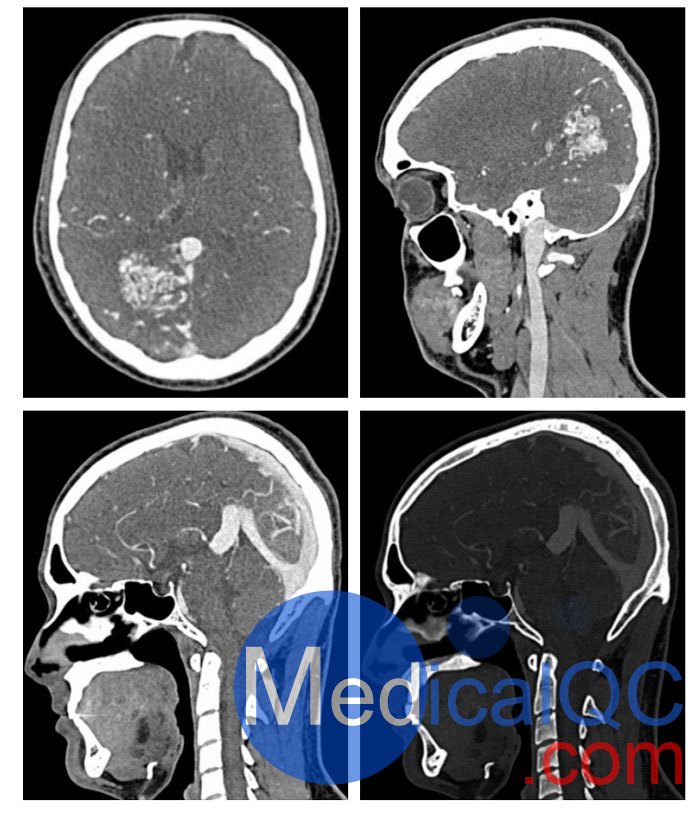

WEK51-04 CTA AVM頭部模體,WEK51-04 CT血管造影頭模模擬動(dòng)脈期造影劑增強(qiáng)頭部(CT 血管造影)。它覆蓋了第五頸椎的頂點(diǎn)。右半球有動(dòng)靜脈畸形。

該模型可用于 CT(包括 CBCT)以評(píng)估和優(yōu)化成像性能以及支持 AI 的診斷。它也適用于培訓(xùn)目的。

該模型提供了對(duì)血管結(jié)構(gòu)、軟組織和骨組織的詳細(xì)和逼真的模擬,包括淋巴結(jié)等小細(xì)節(jié)。空隙中填充著約-160HU的纖維素-聚合物復(fù)合材料。

對(duì)頭頸部血管進(jìn)行逼真的模擬,直至主動(dòng)脈弓、骨骼和軟組織。兩側(cè)頸動(dòng)脈分叉處頸內(nèi)動(dòng)脈鈣化,右側(cè)輕度狹窄。

WEK51-04 CTA AVM頭部模體,WEK51-04 CT血管造影頭模成像效果圖: